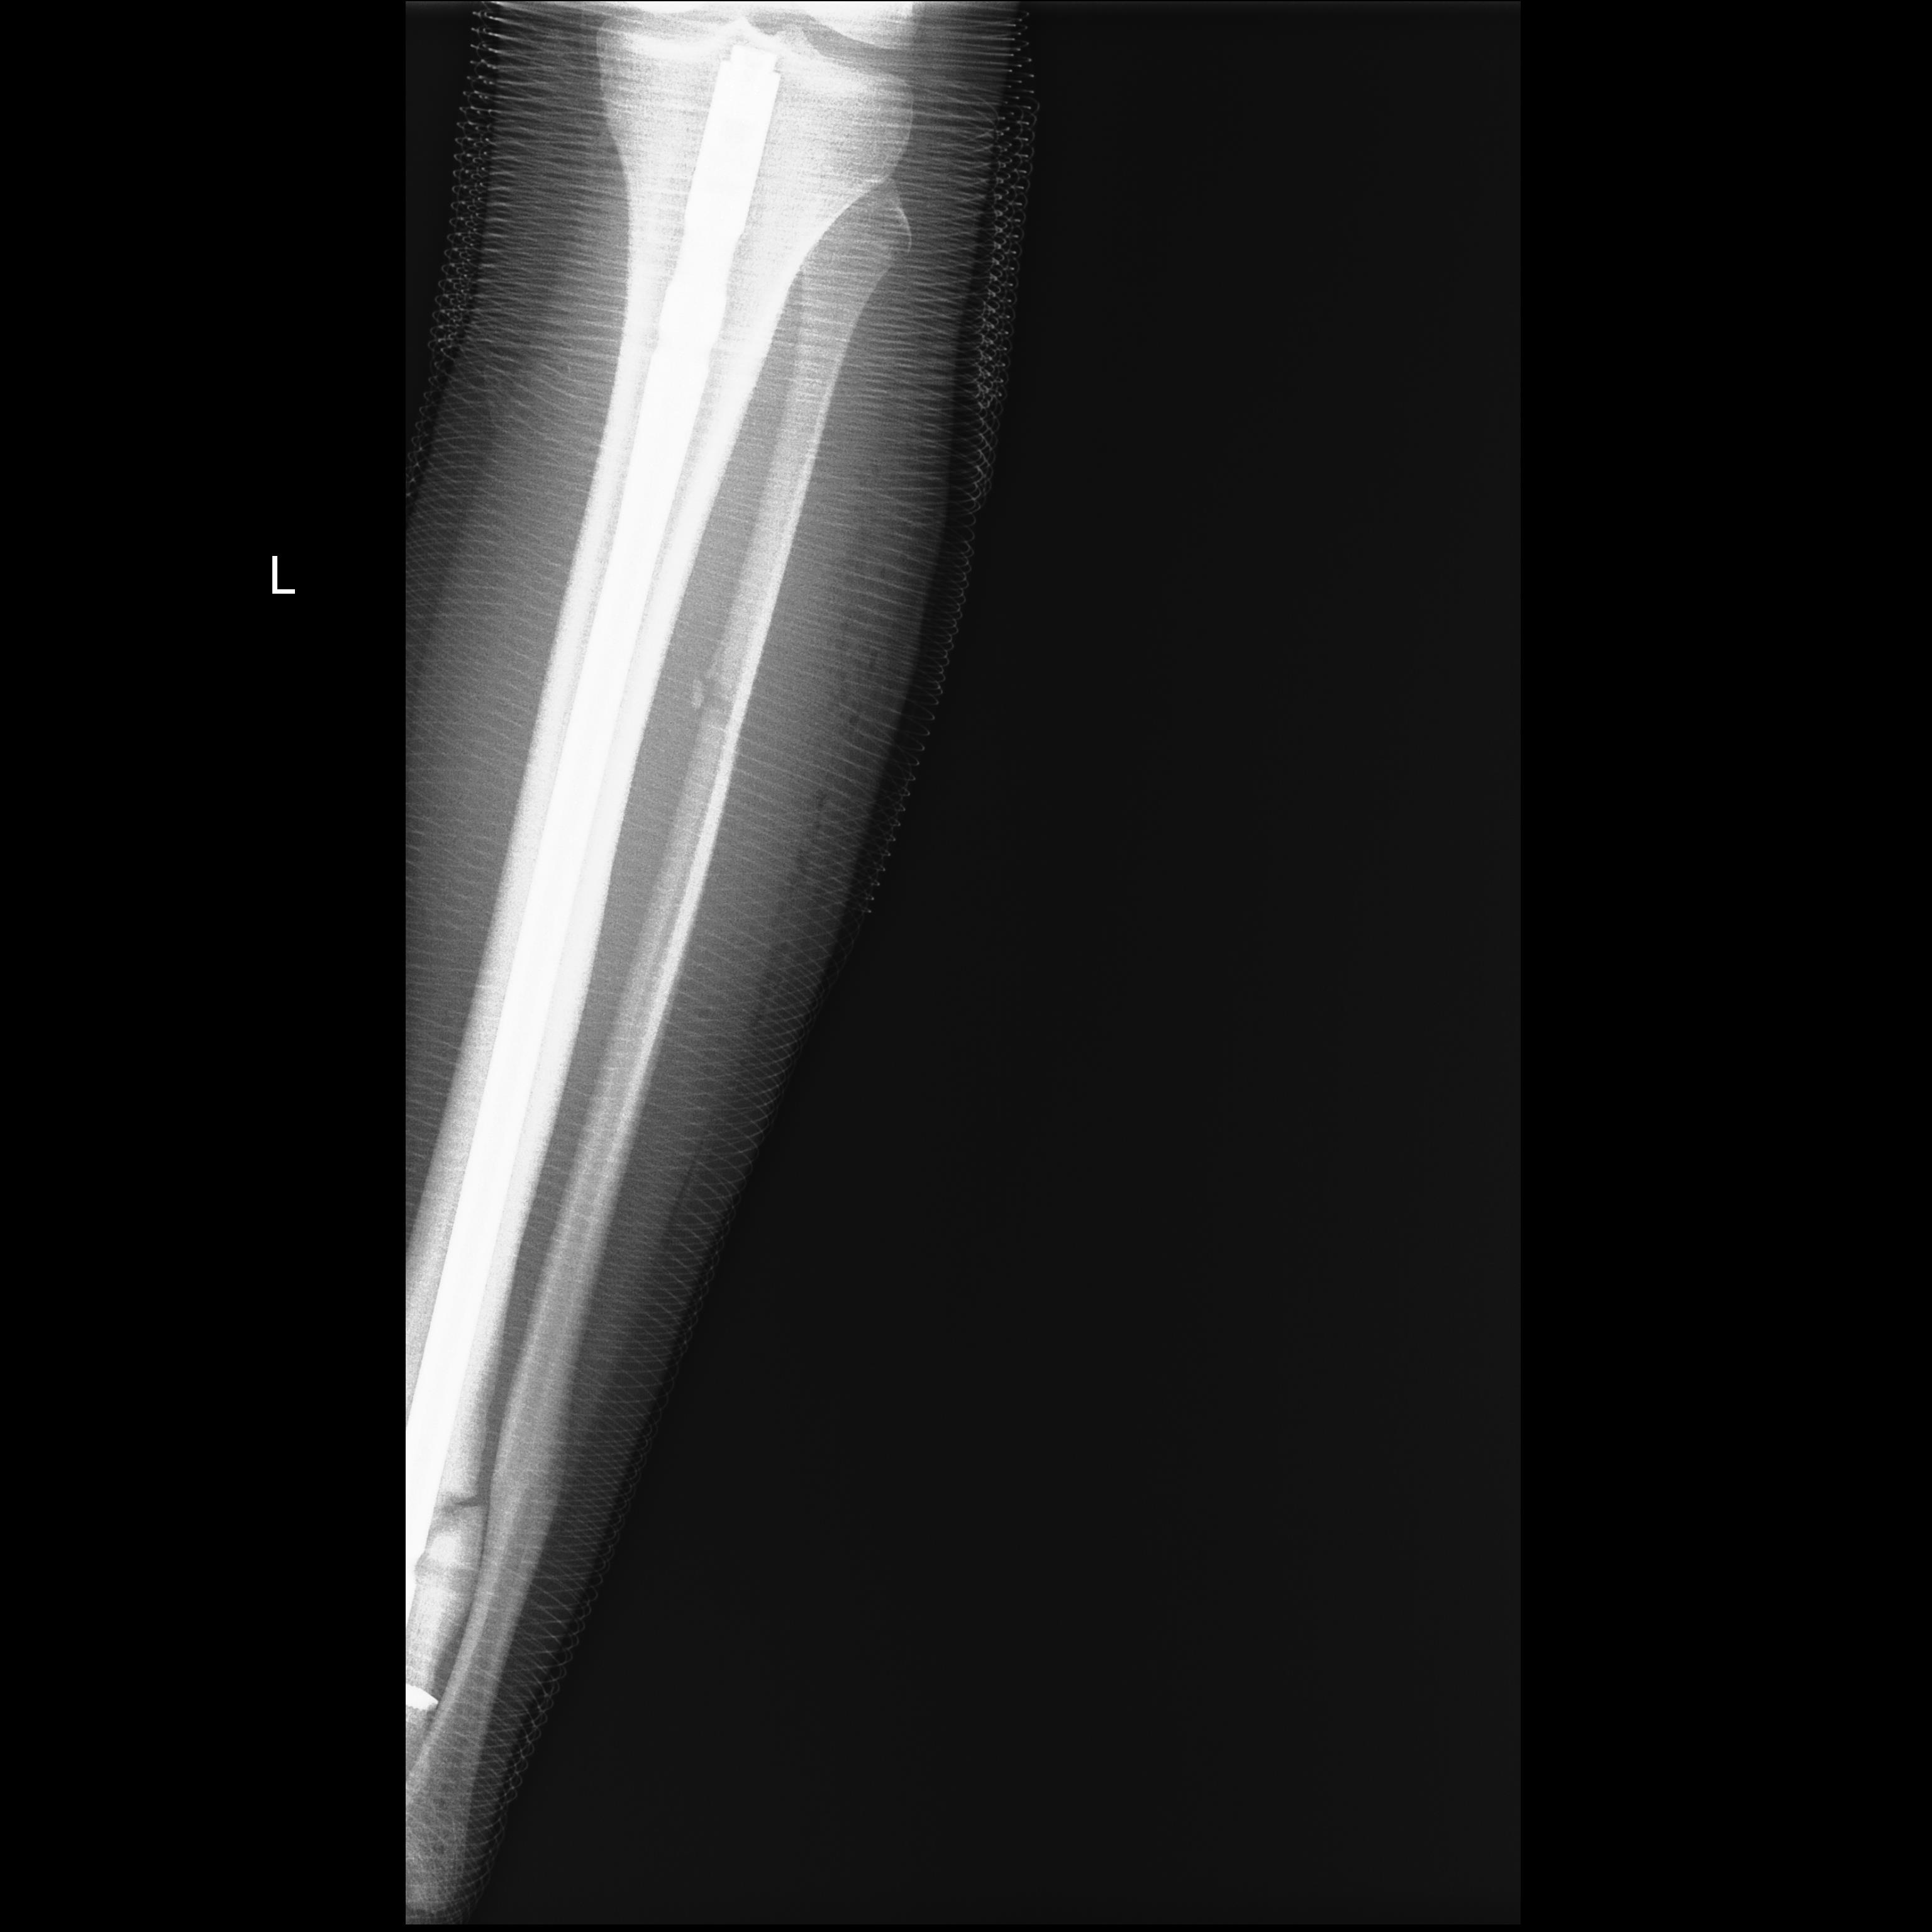

Удалили все, кроме нижнего, винты. Конечно, сделали остеотомию

малоберцовой кости.

"освежили" по Беку зону перелома, ввели PRP

Рекомендована нагрузка до 2 недель на костылях с нарастанием до полной.

Имя     : После удаления1.jpg